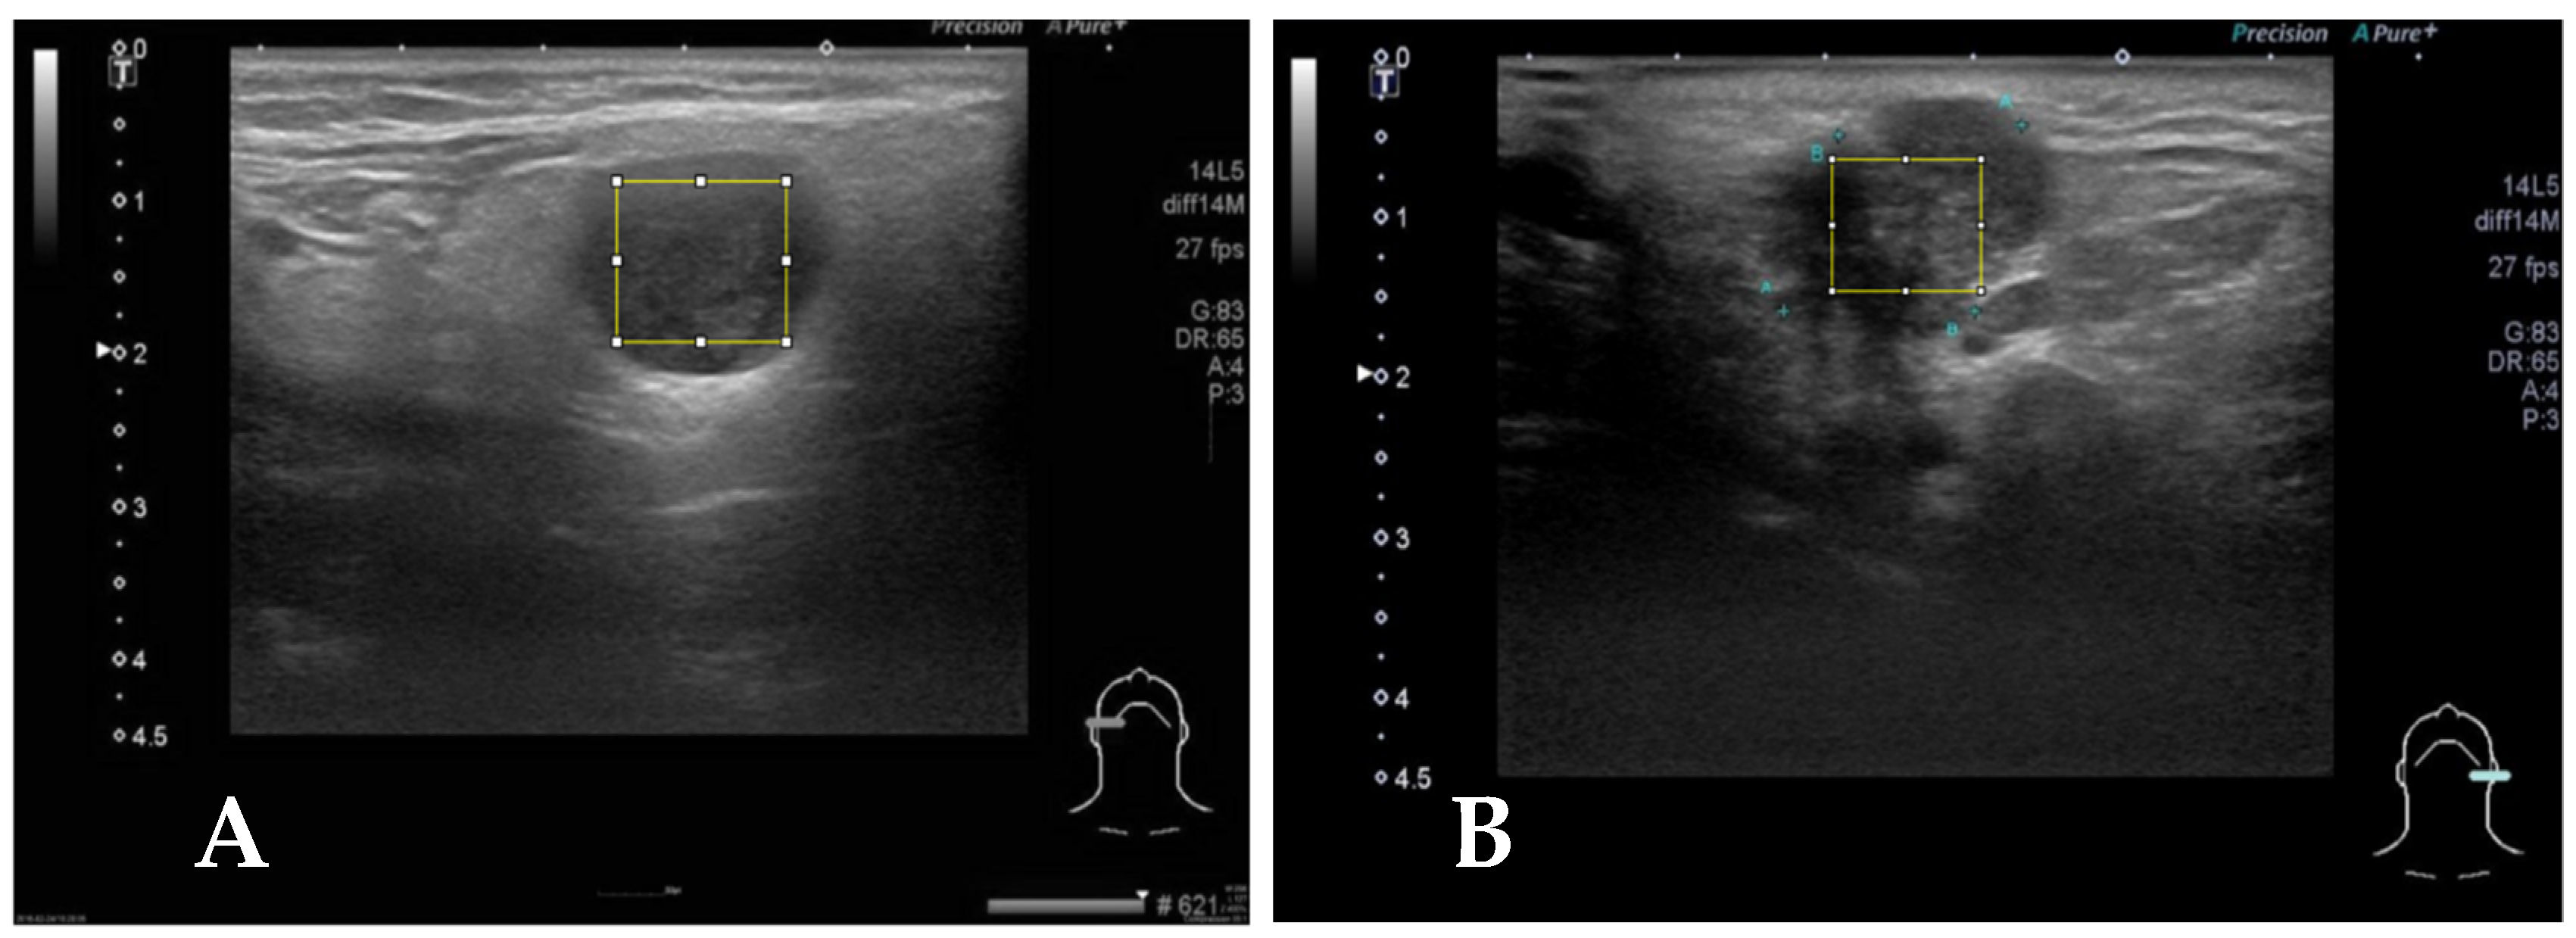

Figure 2.

(A) Case 2, the square block is sampled from a right parotid tumor for GLCM texture analysis by Image J. The pathologic report reveals pleomorphic adenoma. (B) The square block is sampled for GLCM texture analysis from another left parotid tumor, and the pathologic report reveals mucoepidermoid carcinoma.